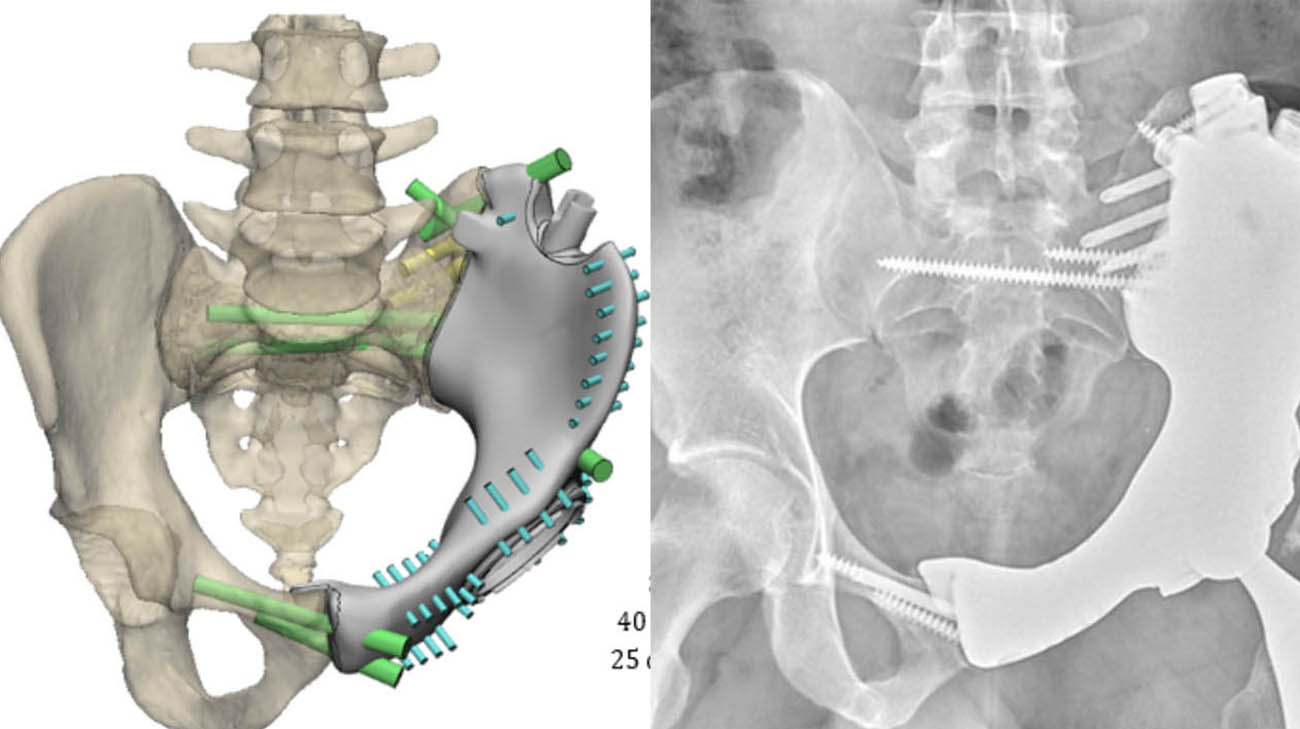

An image and scan of Rayshaun's 3D-printed custom pelvic implant. (Courtesy: Cleveland Clinic)

“Years ago, he would have lost his leg or, at best, not been able to use it because the pelvis would no longer be connected to the leg,” states Dr. Mesko. “But with today’s advanced medical techniques, anything is possible. With Rayshaun, we created specialized guides to aid in accurately resecting the cancer, then engineered and 3D-printed a custom pelvic implant to rebuild the defect. Now we can get rid of the cancer, preserve the leg and restore Rayshaun’s function.”

Working with several engineers and developers, and with colleagues at Cleveland Clinic, Dr. Mesko used numerous scans of Rayshaun’s pelvis to map out every aspect of the surgery – from incision entry points and suture angles to the exact amount and location of the bone and tissue that would need to be removed. Additionally, they used the images to construct a model that would ultimately be used to produce the final 3D-printed pelvic implant.